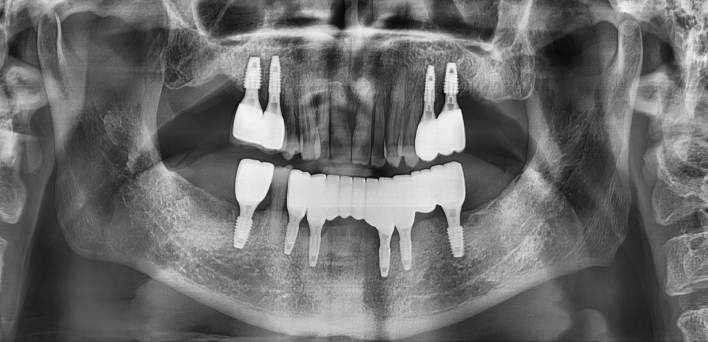

디지털 진단 후 컴퓨터 분석을 통한 모의수술 후 0.1mm 오차 없이 정확한 자리에 식립합니다.

위, 아래 6개씩 식립

디지털 풀아치 임플란트

발치 즉시, 임플란트 식립으로

바로 식사가 가능한 임플란트

발치 즉시, 임시치아 완료

발치 즉시, 식사는 어떻게 할 지 고민되셨나요?

더서울치과의원은 발치 즉시 임플란트 식립으로 일상생활을 지켜드립니다.

더서울치과의원은 다수의 임플란트 수술 경험을 토대로 정확한 디지털 기반 진단,

환자에게 가장 적합한 수술 방법으로 내 치아처럼 오래 사용하는 임플란트를 식립합니다.